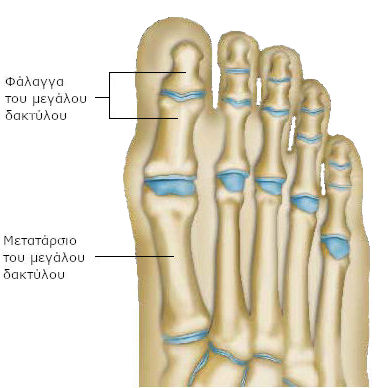

Όλοι οι δάκτυλοι αποτελούνται από δύο ή τρία μικρότερα οστά (φάλαγγες) και συνδέονται με το υπόλοιπο άκρο πόδι μέσω ενός μακρύτερου οστού (μετατάρσιο).

Μεταξύ των δύο οστών, δημιουργείται μια άρθρωση. Περιβάλλεται από ένα είδος σάκου (αρθρικός θύλακος). Σταθερός και μαλακός ταυτόχρονα, συγκρατεί τα δύο οστά στη θέση τους.

Κάθε οστό συγκρατείται επίσης από ένα είδος ελαστικών ιστών: τους συνδέσμους. Τα οστά συνδέονται με τους μυς με προσφύσεις, τους τένοντες, χάρη στους οποίους οι δάκτυλοι μπορούν να λυγίζουν και να τεντώνονται.